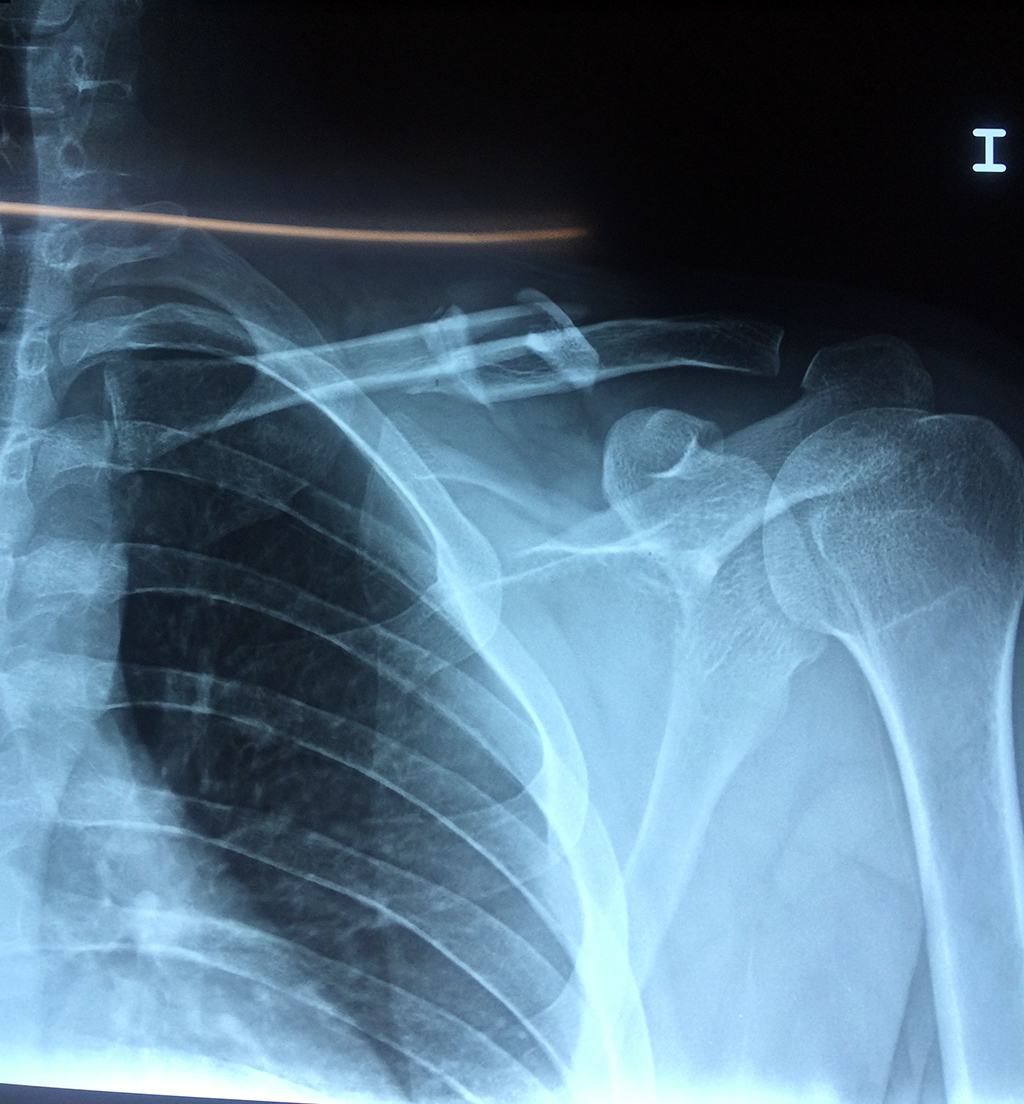

Cirugías de Hombros - Clavícula

La clavícula es un hueso largo, con forma de "S" itálica, situado en la parte anterosuperior del tórax. Junto con la escápula forman la cintura escapular. Se puede palpar por toda su longitud y se extiende del esternón al acromion de la escápula, siguiendo una dirección oblicua lateral y posterior.